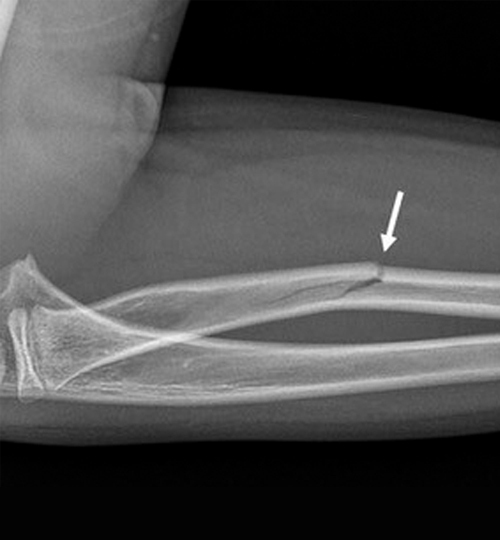

• fracture en bois vert : une corticale est pliée mais continue alors que l’autre est rompue (fig. 4) ;

• fracture « plastique » ou « arcuature » : il n’y a pas de fracture mais une courbure plastique s’étendant sur toute la longueur de l’os (fig. 5) ;